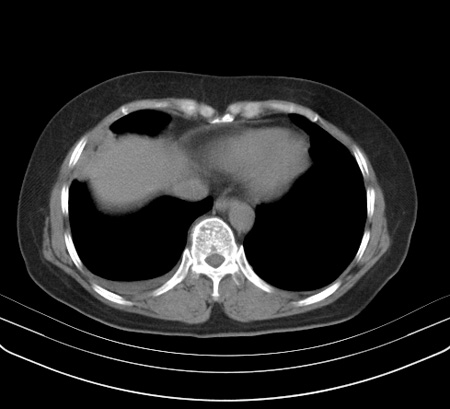

以下是引用余辉在2009-2-19 20:10:00的发言:[br]多考虑急性感染性病变,右中叶尚可见多枚小斑片状影,多为化脓性肺炎,双侧胸腔积液

以下是引用随光逐影在2009-2-19 20:33:00的发言:[br]1)考虑右肺炎症;建议抗炎治疗后复查。2)双侧胸腔积液(以右侧为甚)。

以下是引用花凤凰在2009-2-19 20:46:00的发言:[br]病人有发热,胸痛急性起病,主要病变位于右肺中叶外侧段,呈楔行改变,位于外带胸膜下,考虑为肺梗塞可能!!!!!!!!!!!!!!!!!!!!!!!!!!!!!!!!!!!